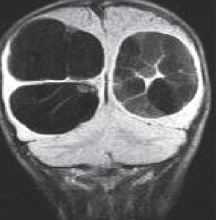

МРТ головного мозга. Т2-взвешенная корональная МРТ. Киста кармана Ратке.

Киста кармана Ратке представляет собой редко встречающееся образование из остатков эмбриональной эктодермы (щель Ратке), расположенное между долями гипофиза. Выявляется в любом возрасте, но чаще в 50-60 лет. Клинические проявления связаны с масс-эффектом. При головного мозга выявляется небольшая (3-5 мм) киста с четким контуром, без отека вокруг, однородная по структуре. Сигнал зависит от содержимого. При серозном содержимом сигнал типично жидкостный, при мукоидном киста светлая на Т1-взвешенных МРТ. В редких случаях киста достигает больших размеров и даже выходит за пределы седла. Стенка кисты иногда усиливается при контрастировании.

Киста кармана Ратке представляет собой редко встречающееся образование из остатков эмбриональной эктодермы (щель Ратке), расположенное между долями гипофиза. Выявляется в любом возрасте, но чаще в 50-60 лет. Клинические проявления связаны с масс-эффектом. При МРТ головного мозга выявляется небольшая (3-5мм) киста с четким контуром, без отека вокруг, однородная по структуре. Сигнал на МРТ головного мозга зависит от содержимого. При серозном содержимом сигнал типично жидкостный, при мукоидном киста светлая на Т1-взвешенных МРТ головного мозга. В 70-80% случаев внутри кисты выявляется неконирастирующийся узелок («пятно») - признак патогномоничный для кисты кармана Ратке. В редких случаях киста достигает больших размеров и даже выходит за пределы седла. Стенка кисты иногда усиливается при МРТ головного мозга с контрастированием. Дифференциальная диагностика при МРТ головного мозга должна проводиться с арахноидадьной и эпидермоидной кистами, тератомой, кистозной аденомой гипофиза и краниофарингиомой. Иногда при МРТ головного мозга киста кармана Ратке напоминает “пустое” турецкое седло. При маленьких размерах кисты ее на до дифференцировать на МРТ с микроаденомой гипофиза.